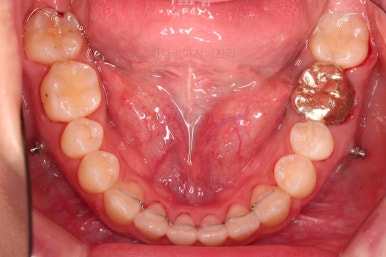

부산치아교정잘하는곳 키다리아저씨치과에서 치료를 종료했을 때의 사진입니다.

위아랫니가 가지런해졌고요.

다시 틀어지지 말라고 적절한 유지장치를 구성합니다.

보철 치아의 위치/크기로 인해 100% 중앙선은 맞기 힘드나 가장 잘 맞추어 놨고, 앞니의 각도도 매우 좋아졌습니다.

아래 앞니도 단순히 머리 부분만 뒤로 눕힌 것이 아니라 뿌리까지 뒤로 당겨왔고요.

교합, 가지런함, 앞니 각도 모두 좋아졌습니다.